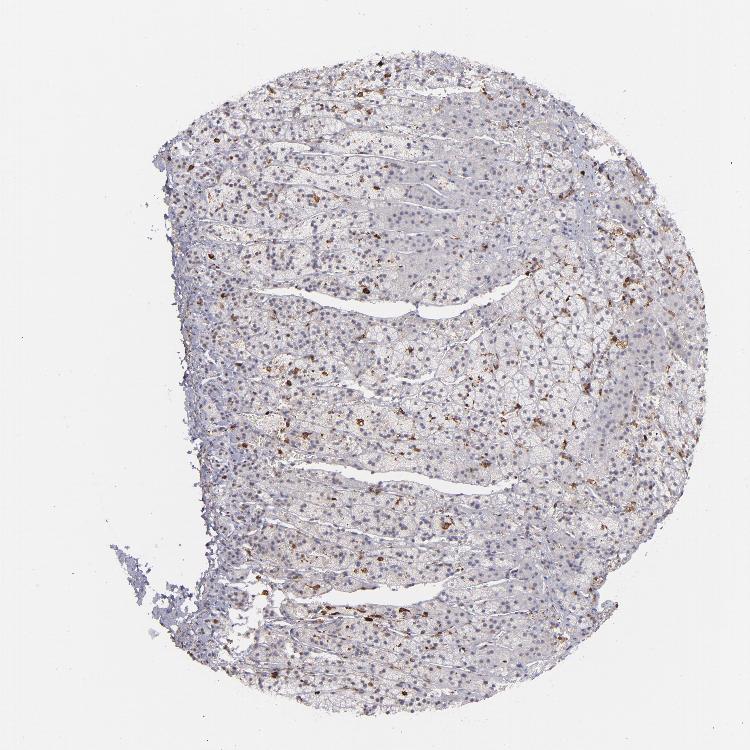

ADRENAL GLAND - Antibody stainingi

Antibody staining in the annotated cell types in the current human tissue is reported as not detected, low, medium, or high, based on conventional immunohistochemistry profiling in selected tissues. This score is based on the combination of the staining intensity and fraction of stained cells.

Each image is clickable and will lead to virtual microscopy that enables deeper exploration of all samples and also displays staining intensity scores, fraction scores and subcellular localization as well as patient and tissue information for each sample.

Antibody HPA002327Antibody HPA006040Antibody CAB022160

Glandular cells Not detectedNot detectedNot detected